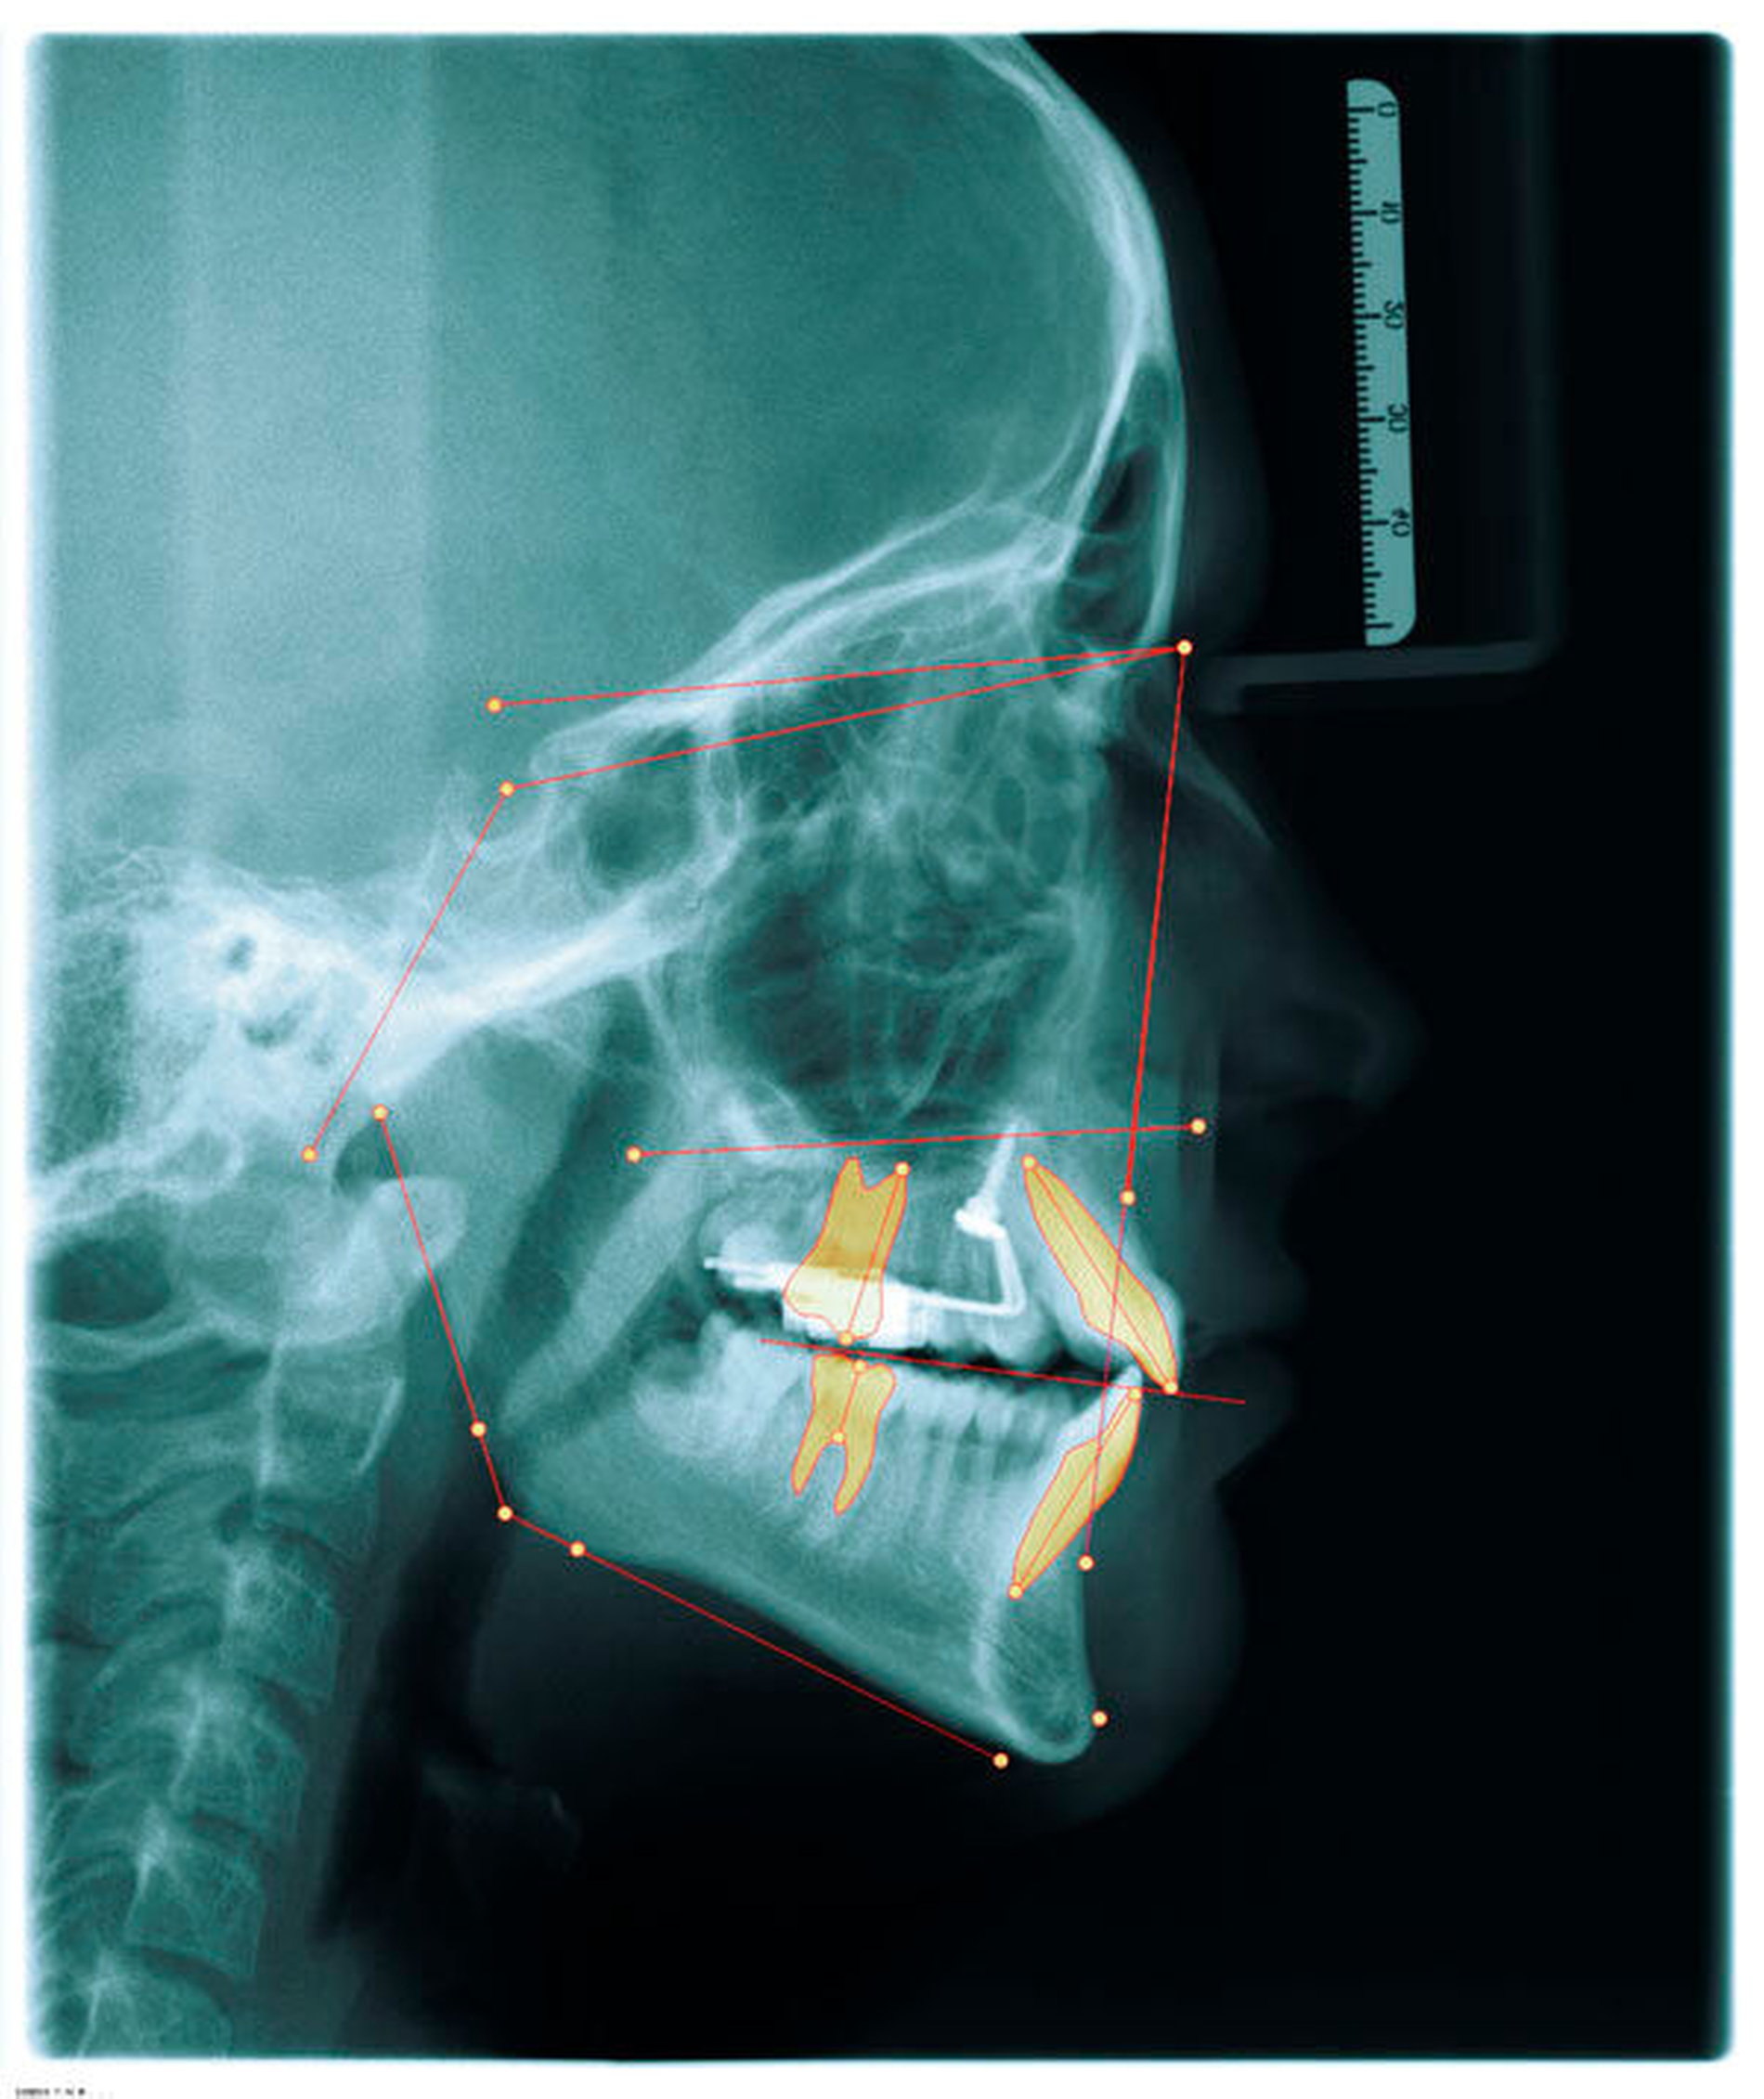

Wie beim Einbringen von Zahnimplantaten schaffen die computergestützte Planung und die Verwendung von Schablonen auch bei der Insertion von Mini-Implantaten mehr Sicherheit für den Behandlungserfolg. Für die zunächst virtuelle Insertion werden ein Abdruck oder ein Scan sowie ein Röntgenbild (FRS oder DVT) überlagert [De Gabriele, 2017] (Abbildungen 1 und 2, Easy Driver Software, Labor Uniontech, Parma/IT). Während in einem normalen Fall das FRS ausreicht, ist bei schwierigen Situationen (zum Beispiel LKG-Spalte, palatinal verlagerte Eckzähne) sicherlich die Anfertigung eines DVTs empfehlenswert. Basierend auf der computergestützten Planung wird eine Insertionsschablone per Rapid-Prototyping-Verfahren (RKS Labor, Rastede/D, Abbildung 3) zusammen mit dem gewünschten kieferorthopädischen Gerät im zahntechnischen Labor hergestellt.

Das Prinzip einer CAD/CAM-gesteuerten Insertion wird anhand einer zehnjährigen Patientin mit einem Platzmangel für die oberen Eckzähne dargestellt (Abbildungen 4a, 4b). Die Behandlung begann mit dem Anpassen von Molarenbändern und einem Silikon-Abdruck des Oberkiefers, der mit dem FRS an das zahntechnische Labor gesendet wurde und dort mit dem FRS der Patientin überlagert wurde. So konnten geeignete Insertionsstellen virtuell geplant werden (Abbildungen 1, 2a, 2b). Nach Rücksprache mit dem Behandler bezüglich der Mini-Implantatpositionen erfolgte die Herstellung der Insertionsschablone (Abbildung 3). Parallel dazu wurde auch der Beneslider [Wilmes, 2010] hergestellt, der zusammen mit der Insertionsschablone geliefert wurde (Abbildung 5). Mithilfe der Insertionsschablone konnten die Mini-Implantate und der Beneslider im selben Termin eingesetzt werden (Abbildungen 6, 7a, 7b). Nach 10 Monaten Distalisierung waren die Molaren in der Zielposition und es war ausreichend Platz für die Eckzähne vorhanden (Abbildungen 8a, 8b), so dass Brackets für die zweite Phase der Behandlung eingesetzt werden konnten. Die Multibracket-Apparatur (Abbildung 9) konnte nach 12 Monaten entfernt werden (Abbildungen 10, 11).